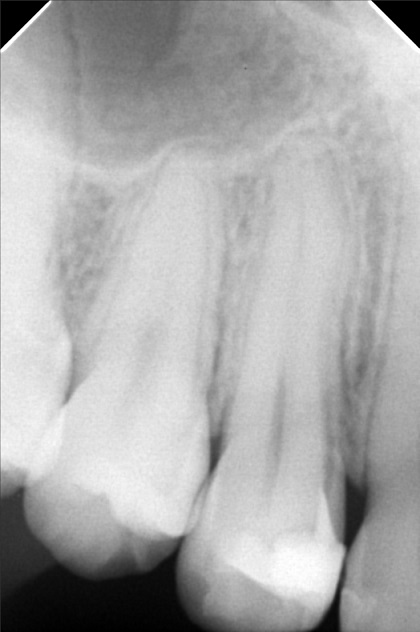

- 08/15/21- adj 16*22UL 18niti 34 09/18/21 - adj. 34^ for removal- for resto 22/34 10/16/21 - REMOVAL OF BRACES RESTO: 17 CAOH occ/14 MO mta/13 LINGUAL DISTAL ESTHETIC 23/22 ALL INCISAL RESHAPING 10/22/21 -lingual retainer up and down wiyh vacuum retainer 3/05/22 LC 14 Mesial + CAOH/ Op 09/08/22 - OP (light) Resto #15 05/13/23- OP(L) For resto #46 06/14/25 OP mild LC #25 fiber, CaoH,ozone,xray 05/21/26 OP